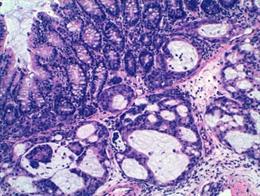

Tumor (Archivo)

Tumor (Archivo) - IDIBELL - Archivo